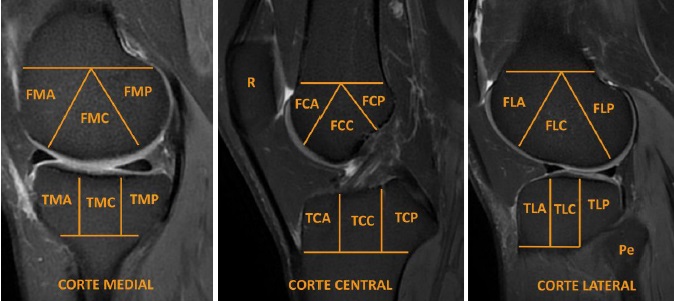

Análisis de imágenes

Se evaluaron de forma independiente los estudios de resonancias magnéticas para detectar la presencia de edema óseo (0 = no, 1 = sí) en la tibia, fémur y la rótula, realizando las adquisiciones de resonancia magnética con reconstrucciones en planos axial, sagital y coronal ponderadas en las secuencias T1, T2, STIR. Para el estudio de la articulación se dividió en 20 regiones anatómicas (Figura 1), utilizando un método de segmentación para la evaluación del edema óseo. La evaluación se realizó por médicos especializados en imágenes musculoesqueléticas, quienes cuentan un alto nivel de formación y entrenamiento en el diagnóstico de patologías articulares de la rodilla, estableciéndose los siguientes protocolos estudio:

IV. Análisis de imágenes. Se revisaron de forma independiente los estudios de resonancias magnéticas para detectar la presencia de edema óseo. Para el estudio de la articulación se dividió en 20 regiones anatómicas como método de segmentación. La evaluación fue realizada por médicos especializados en imágenes musculoesqueléticas, quienes cuentan un alto nivel de formación y entrenamiento en el diagnóstico de patologías articulares de la rodilla.